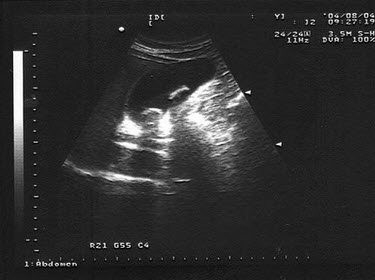

女,28岁,经常上腹不适。声像图如图所示,诊断为()A: 胆囊蛔虫B: 胆囊结石C: 胆囊腺瘤D: 胆囊内胆汁淤积E: 胆囊癌

女,28岁,经常上腹不适。声像图如图所示,诊断为()

- A: 胆囊蛔虫

- B: 胆囊结石

- C: 胆囊腺瘤

- D: 胆囊内胆汁淤积

- E: 胆囊癌